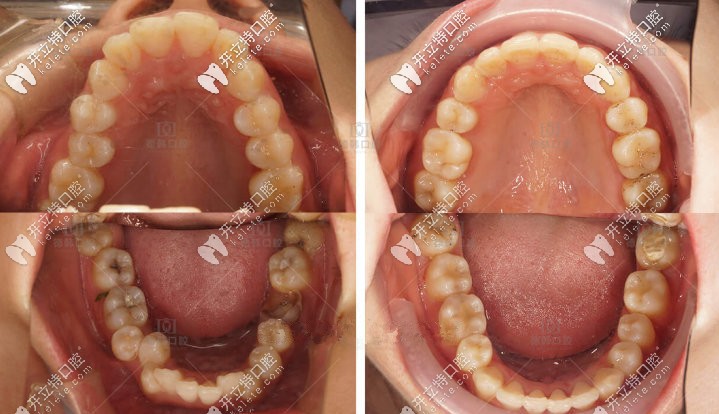

歐巴的口內(nèi)照,牙齒齊了很多撒

歐巴的口內(nèi)照,牙齒齊了很多撒▲